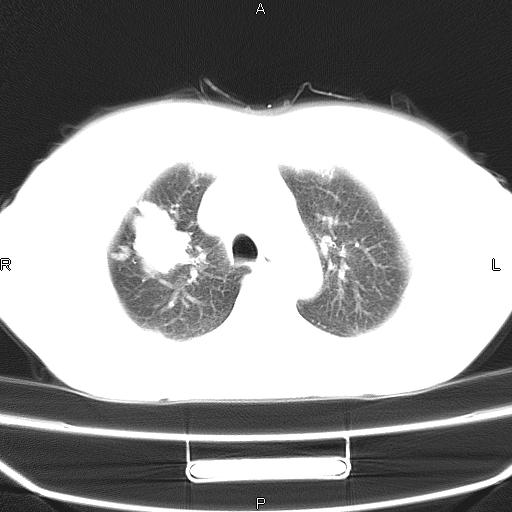

患者,女,66岁。健康体检胸部透视发现右上肺片状阴影。既往无不适,患者自诉三个月前曾有低热病史体温37.5左右一周。用药后缓解。至今无其它不适。请老师们指导指导。

考虑:右肺上叶周围型肺癌(分叶状肿块+砂粒状钙化+胸膜尾征)。

病灶见明显分叶、大小较大(大于3cm?),老年人,多考虑:肺癌,建议穿刺活检。

典型的中心型肺癌,尖段支气管阻塞。

右肺上叶周围型肺癌可能性大。

考虑:右肺上叶周围型肺癌